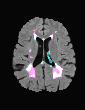

In recent years, data-driven machine learning (ML) methods have revolutionized the computer vision community by providing novel efficient solutions to many unsolved (medical) image analysis problems. However, due to the increasing privacy concerns and data fragmentation on many different sites, existing medical data are not fully utilized, thus limiting the potential of ML. Federated learning (FL) enables multiple parties to collaboratively train a ML model without exchanging local data. However, data heterogeneity (non-IID) among the distributed clients is yet a challenge. To this end, we propose a novel federated method, denoted Federated Disentanglement (FedDis), to disentangle the parameter space into shape and appearance, and only share the shape parameter with the clients. FedDis is based on the assumption that the anatomical structure in brain MRI images is similar across multiple institutions, and sharing the shape knowledge would be beneficial in anomaly detection. In this paper, we leverage healthy brain scans of 623 subjects from multiple sites with real data (OASIS, ADNI) in a privacy-preserving fashion to learn a model of normal anatomy, that allows to segment abnormal structures. We demonstrate a superior performance of FedDis on real pathological databases containing 109 subjects; two publicly available MS Lesions (MSLUB, MSISBI), and an in-house database with MS and Glioblastoma (MSI and GBI). FedDis achieved an average dice performance of 0.38, outperforming the state-of-the-art (SOTA) auto-encoder by 42% and the SOTA federated method by 11%. Further, we illustrate that FedDis learns a shape embedding that is orthogonal to the appearance and consistent under different intensity augmentations.